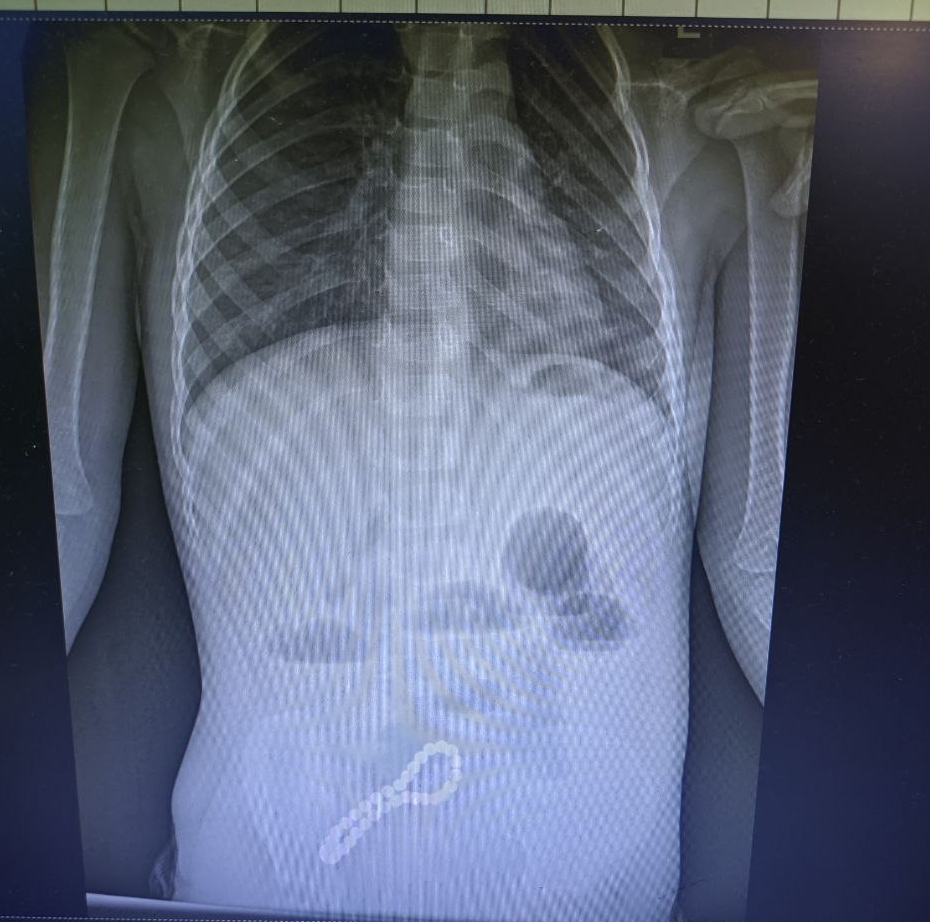

Хирурги заподозрили нарушение функций кишечника. Рентгенограмма подтвердила предположения. Врачи поставили диагноз – инородное тело в кишечнике. Его нужно было удалять.

«Было принято решение об операции. Мы провели минилапаротомию (хирургическое вмешательство, при котором через разрез передней брюшной стенки производится доступ к внутренним органам живота). И увидели, что магнитами, которые притянулись друг к другу, соединены петли кишки, в ее стенке –отверстия. В ходе операции удалили все 30 магнитных бусин: 29 маленьких и одну большую. Сейчас ребенок поправился. Его жизни и здоровью ничего не угрожает», – рассказал заведующий детским хирургическим отделением ОДКБ им. Н.В. Дмитриевой, главный внештатный хирург Минздрава Рязанской области Олег Ларькин.